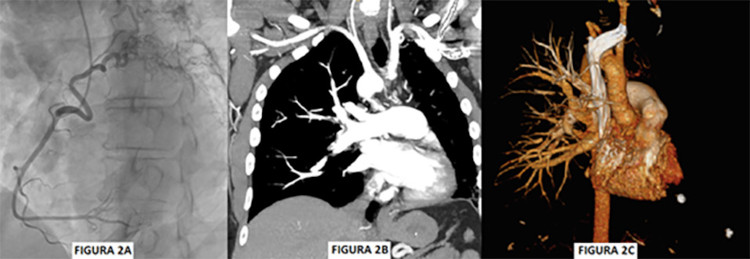

En la cinecoronariografía se informa: arterias coronarias epicárdicas sin lesiones obstructivas, secuestro de la Coronaria Derecha (CD) hacia parénquima pulmonar homolateral. Arco aórtico derecho. (Figura 2A)

La angiotomografía pulmonar pone en evidencia agenesia de la rama pulmonar izquierda principal. Desviación homolateral del mediastino y grandes vasos. Arco aórtico derecho (Figura 1 B. Imagen de falta de relleno en la rama principal segmentaria y subsegmentaria pulmonar derecha compatible con tromboembolismo pulmonar (TEP) agudo). Campo pulmonar izquierdo hipoplásico. Incremento de tronco de arteria pulmonar y cavidades cardíacas derechas. (Figura 2B-2C)